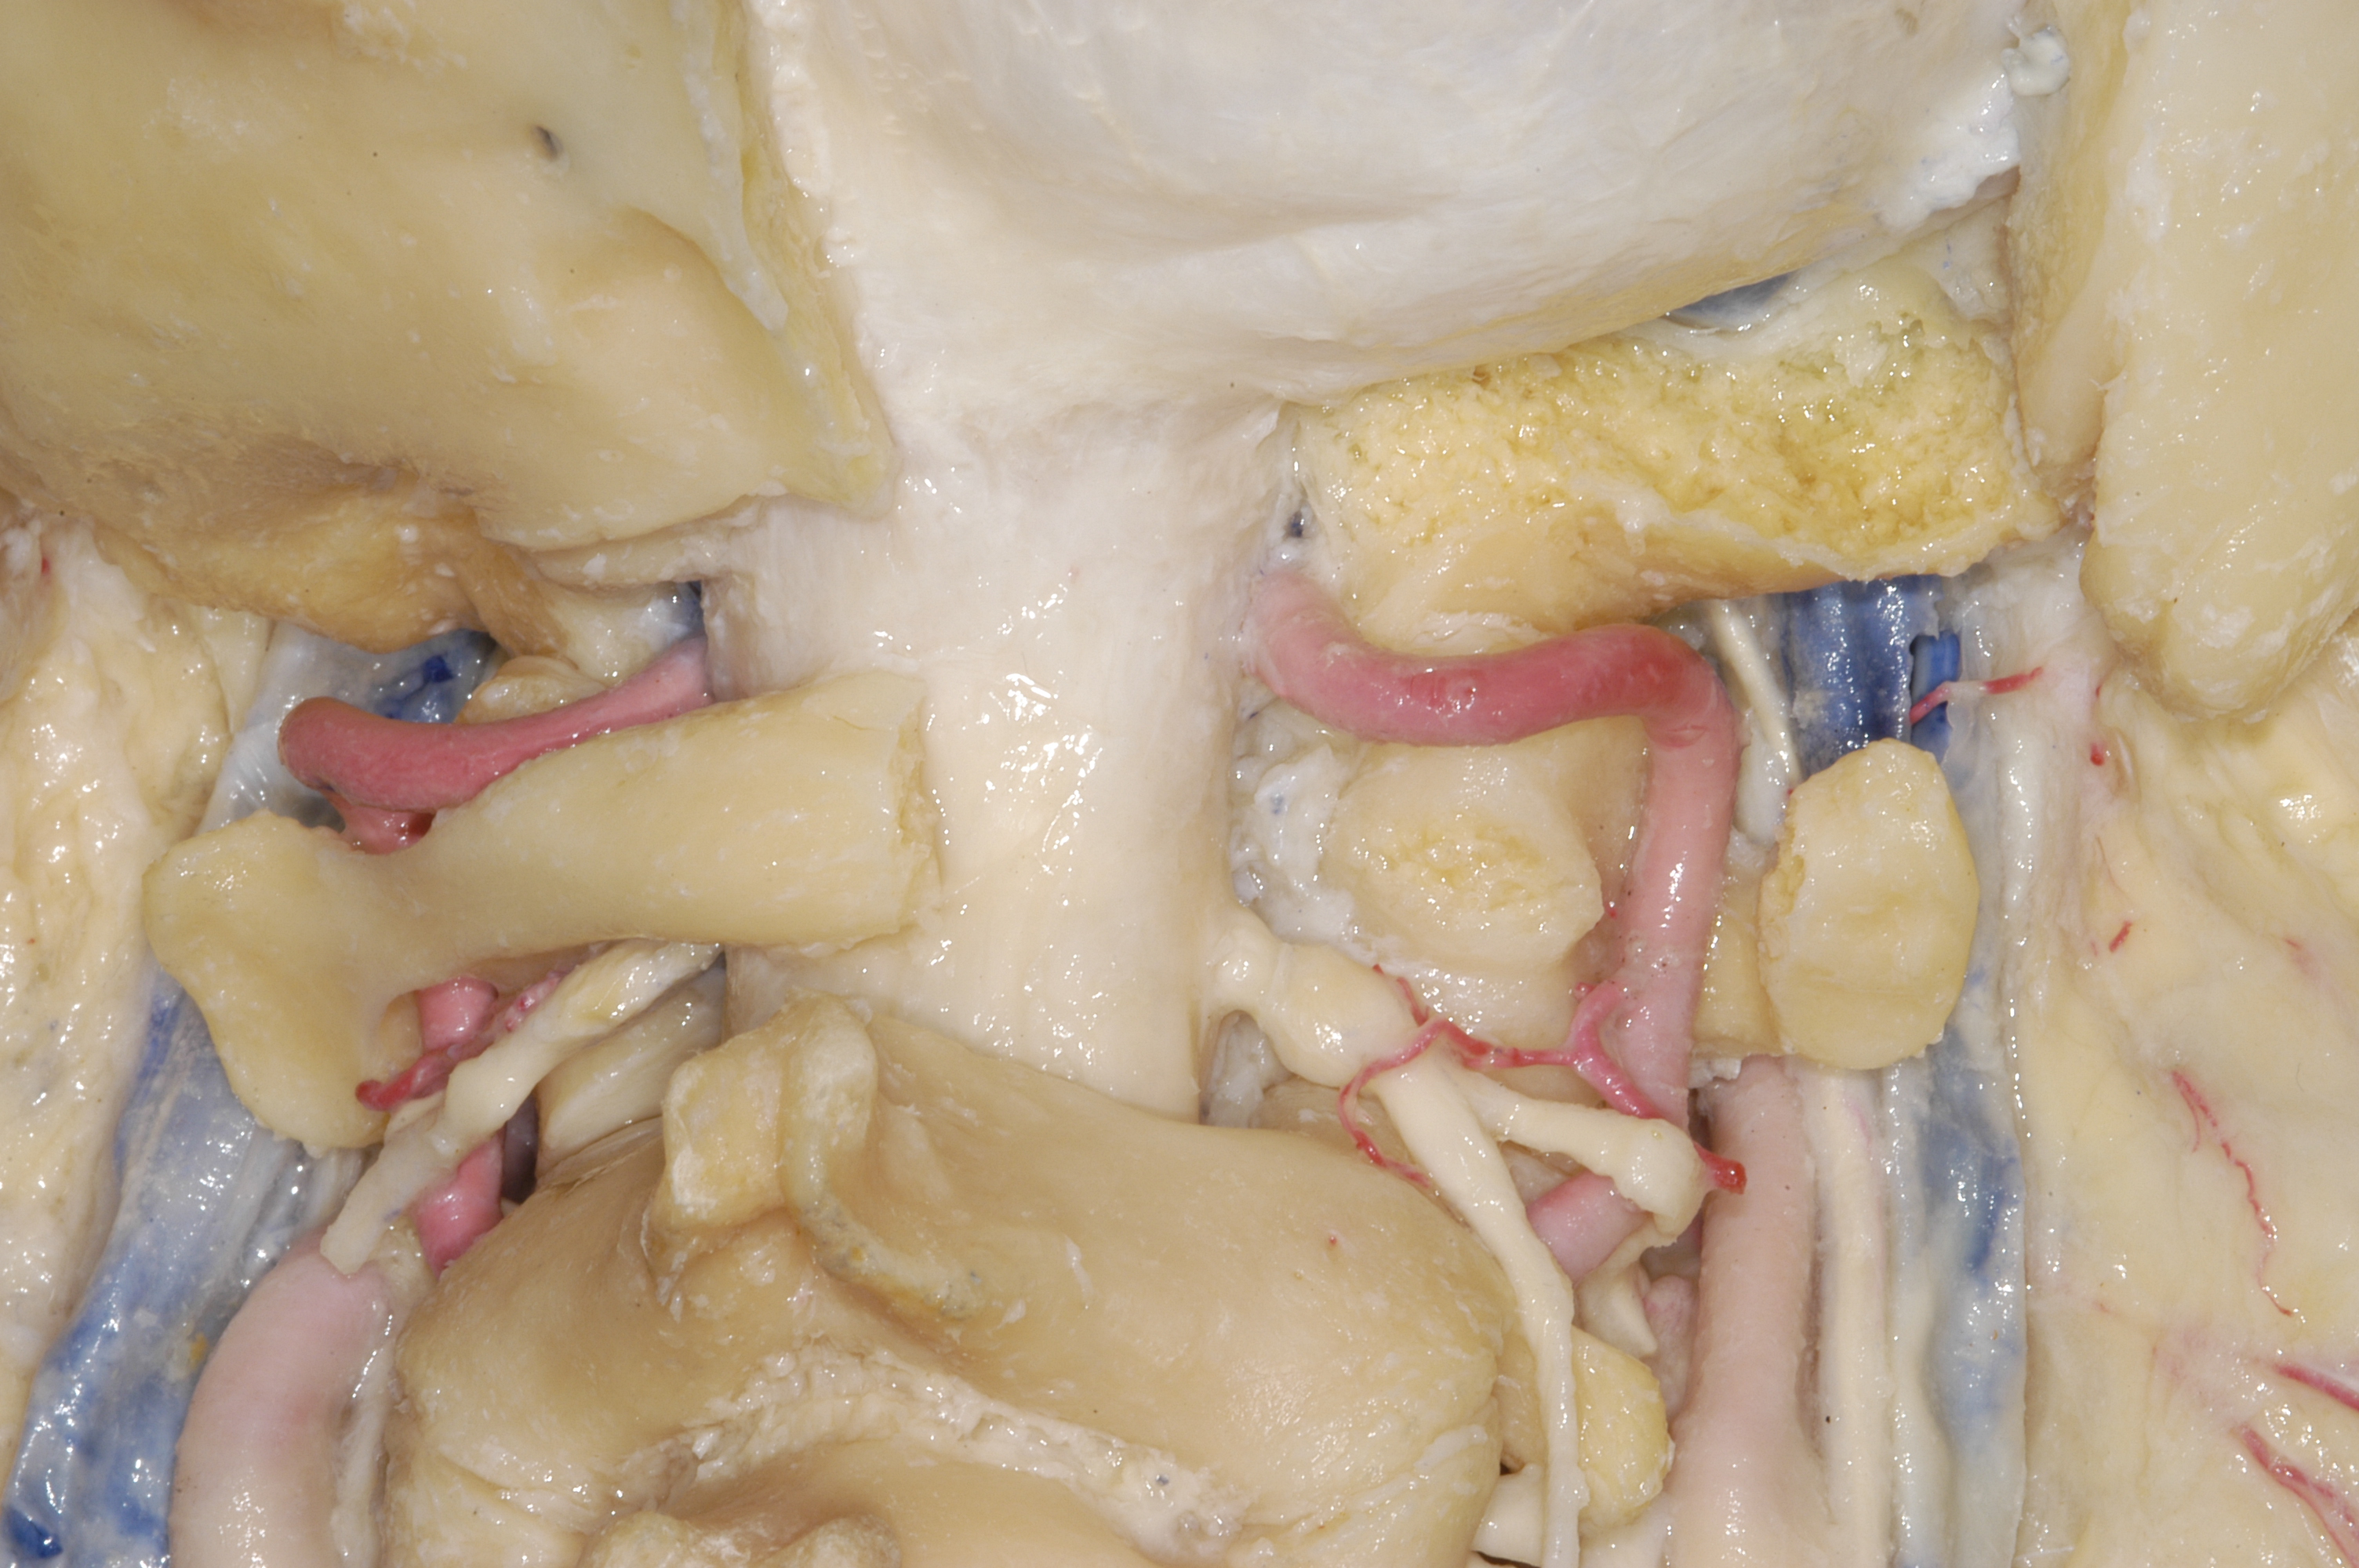

舌下神经管骨性结构

远外侧经髁上开颅逐步过程

有时候会用椎动脉移位,对舌下神经管和颈静脉孔区暴露更好

因为颈静脉孔区毗邻舌下神经管区,所以远外侧髁旁入路和髁上入路都是用耳后C型切口。颈静脉孔区注重暴露颈静脉球部,舌下神经管区注重暴露枕髁。